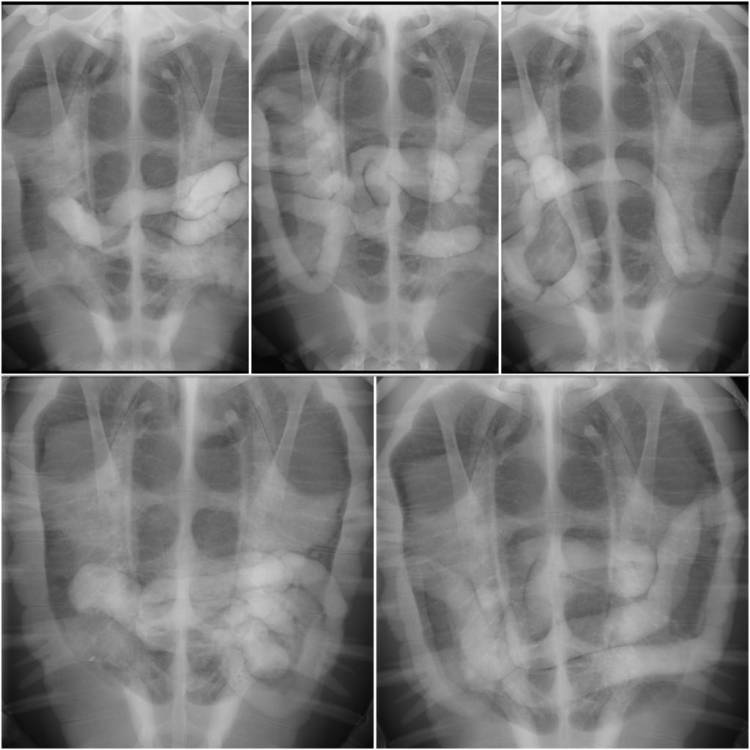

We grew quite concerned about this and X-rayed her to find out more. It turned out that Moya had impaction; her gut wasn’t working properly so nothing was moving. We thought this may have been caused by a blockage. An X-ray contrast study was started and she was taken for an MRI scan. No clear obstruction was revealed, and Moya started pooping soon after that - we thought she was out of the woods.

However, in late February, Moya again stopped pooping. After another MRI and contrast study, it was determined that she had air bubbles in her gut, this was due to a lack of peristalsis (the movement your intestines make to push things along). Even though she had started pooping after the previous scans, her intestines were still struggling to recover.